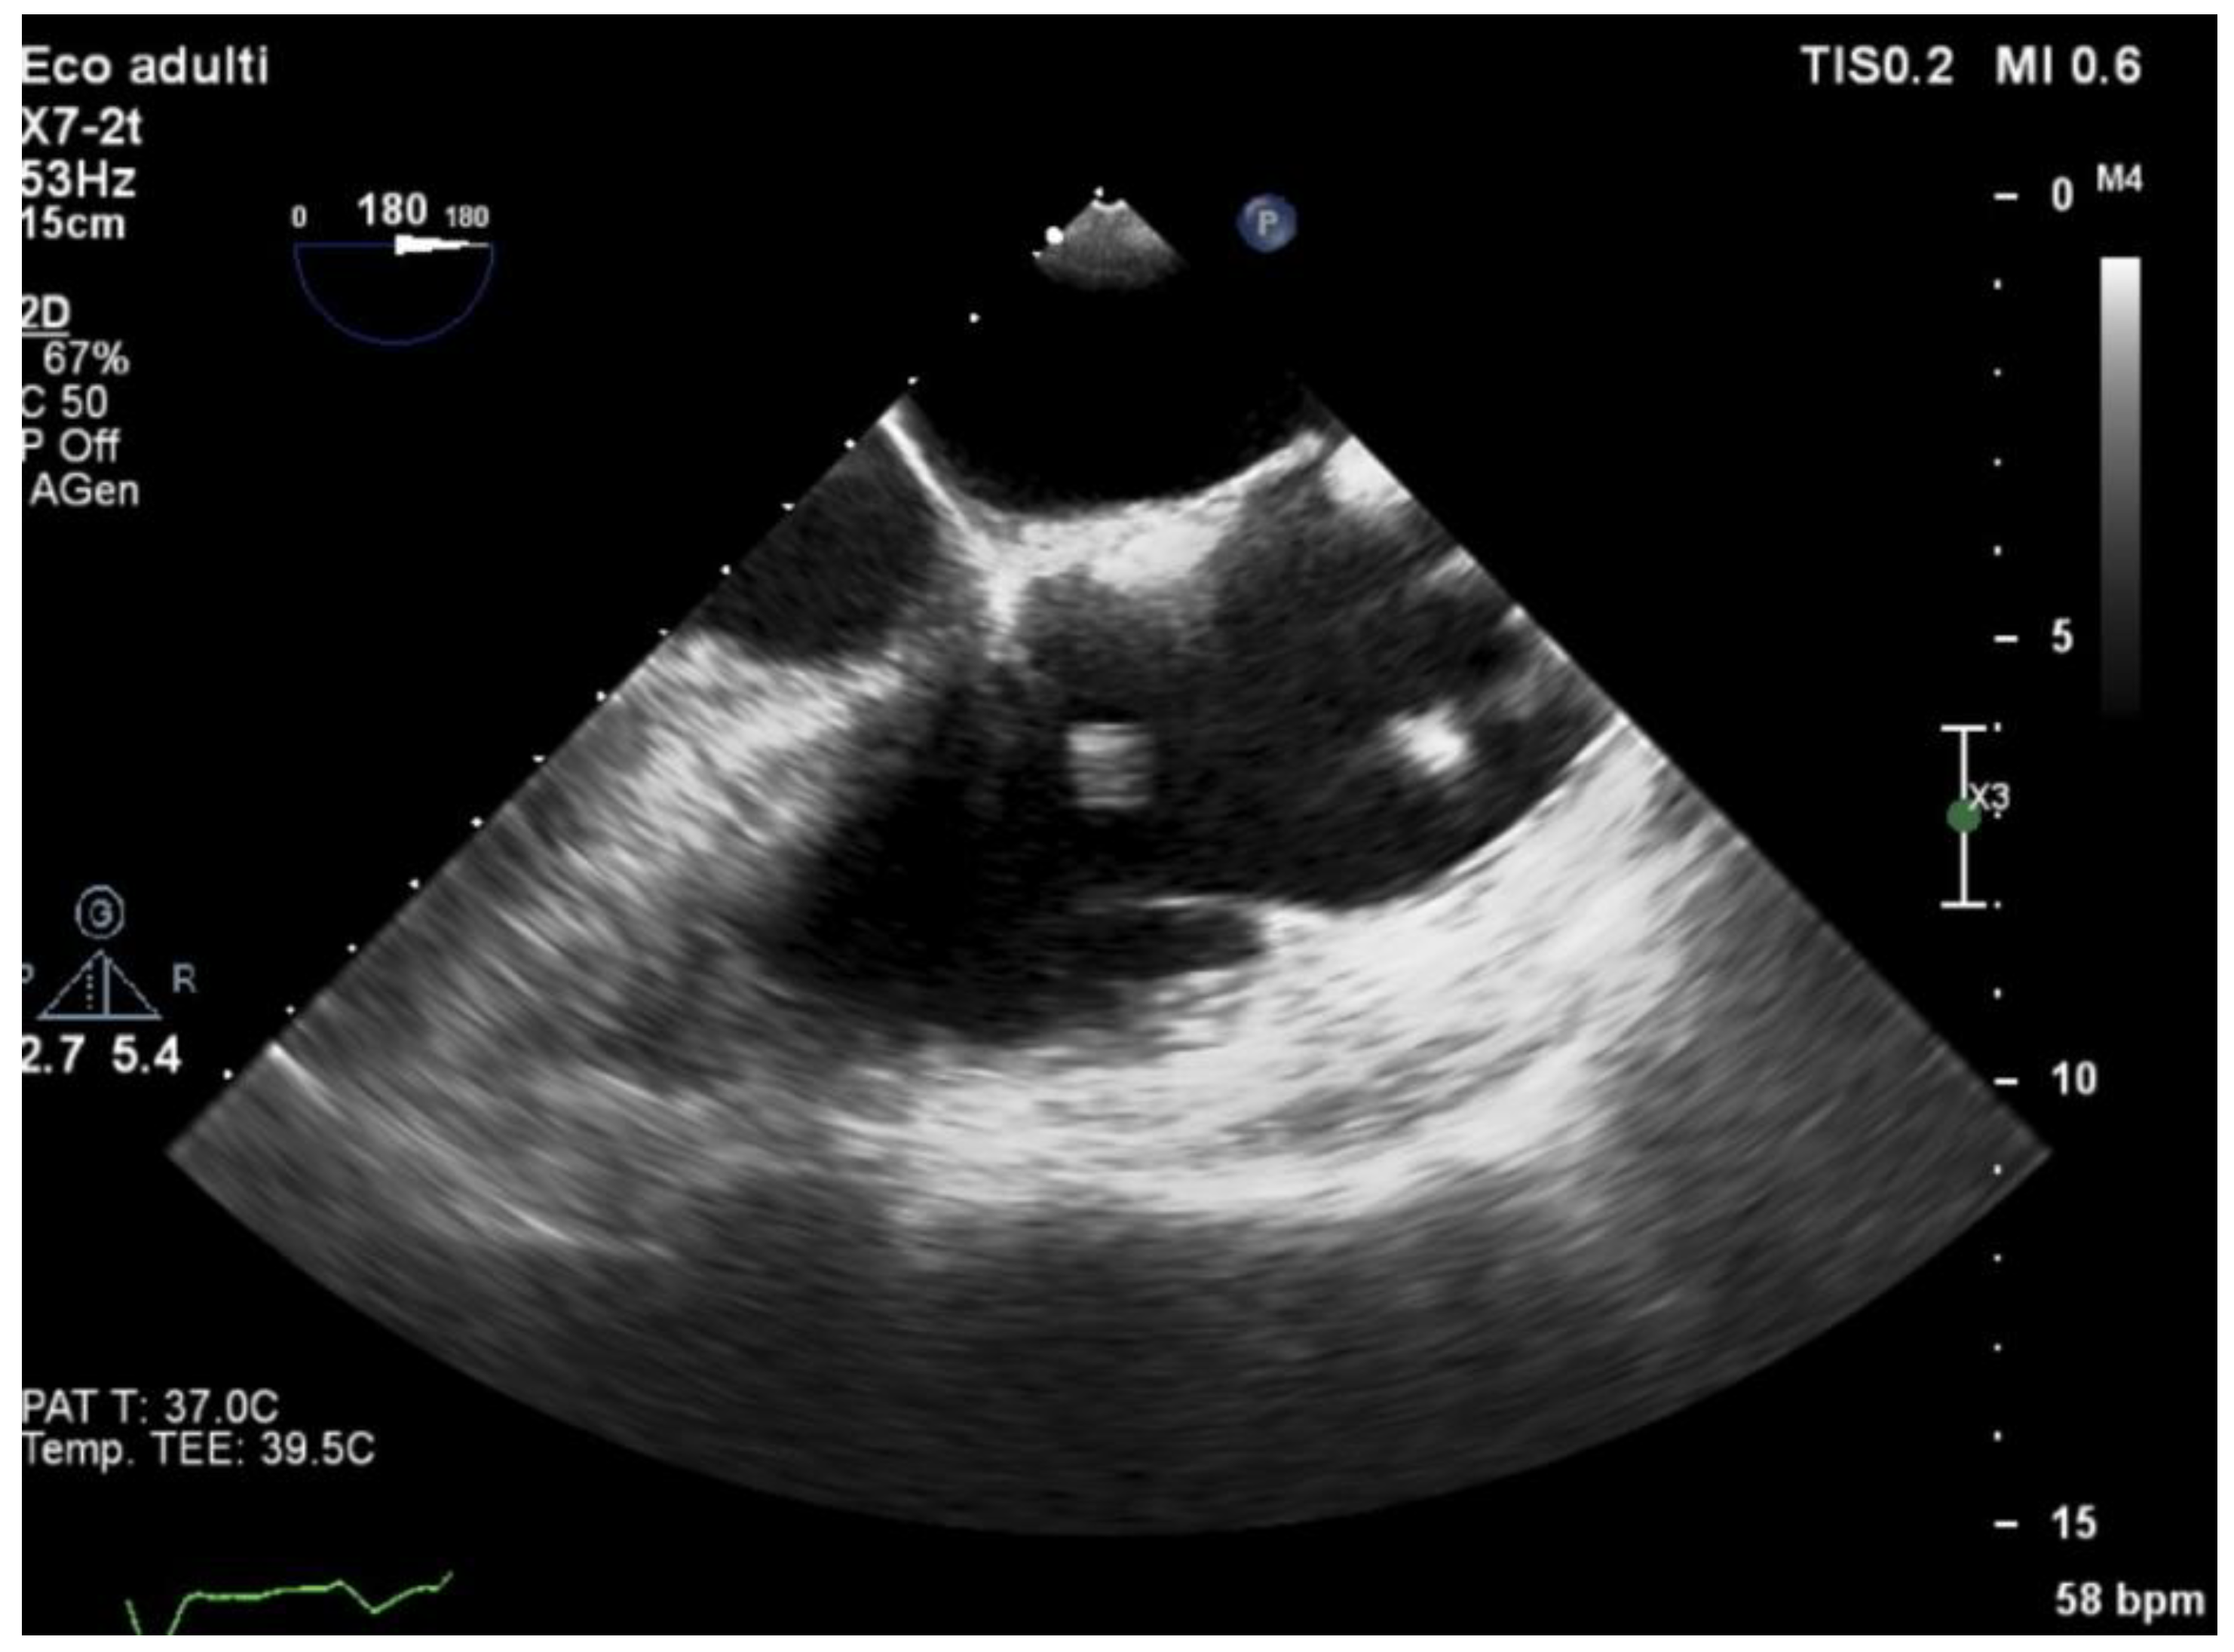

3.5. Echocardiography and Localization of IE